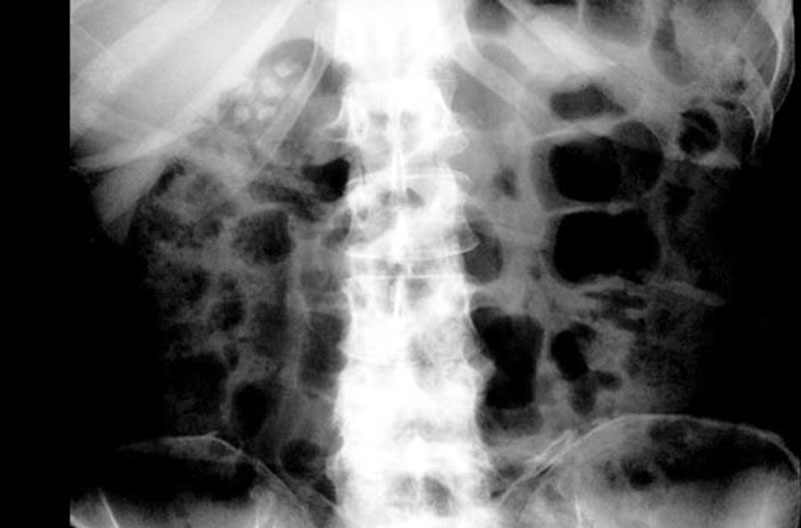

Gallstones

1. Gallstones